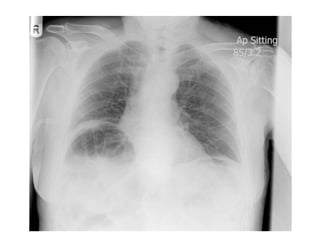

Technical aspects of viewing a PA film

• Centering – medial ends of clavicle equidistant from

spinous process at t4/5- always look for gastric

bubble,aortic arch and heart to confirm normal situs.

• Penetration – disc spaces+vertebral bodies visible

down to t8/9

• Degree of Inspiration – full inspiration ant. Ends of 6th

rib or post ends of the 10th rib on right

hemidiaphragm. On expiration larger cardiac shadow

and basal opacity due to crowding of normal vascular

markings.